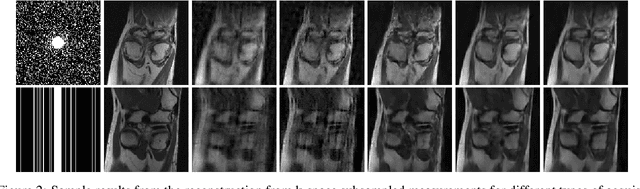

Abstract:There are various inverse problems -- including reconstruction problems arising in medical imaging -- where one is often aware of the forward operator that maps variables of interest to the observations. It is therefore natural to ask whether such knowledge of the forward operator can be exploited in deep learning approaches increasingly used to solve inverse problems. In this paper, we provide one such way via an analysis of the generalisation error of deep learning methods applicable to inverse problems. In particular, by building on the algorithmic robustness framework, we offer a generalisation error bound that encapsulates key ingredients associated with the learning problem such as the complexity of the data space, the size of the training set, the Jacobian of the deep neural network and the Jacobian of the composition of the forward operator with the neural network. We then propose a 'plug-and-play' regulariser that leverages the knowledge of the forward map to improve the generalization of the network. We likewise also propose a new method allowing us to tightly upper bound the Lipschitz constants of the relevant functions that is much more computational efficient than existing ones. We demonstrate the efficacy of our model-aware regularised deep learning algorithms against other state-of-the-art approaches on inverse problems involving various sub-sampling operators such as those used in classical compressed sensing setup and accelerated Magnetic Resonance Imaging (MRI).